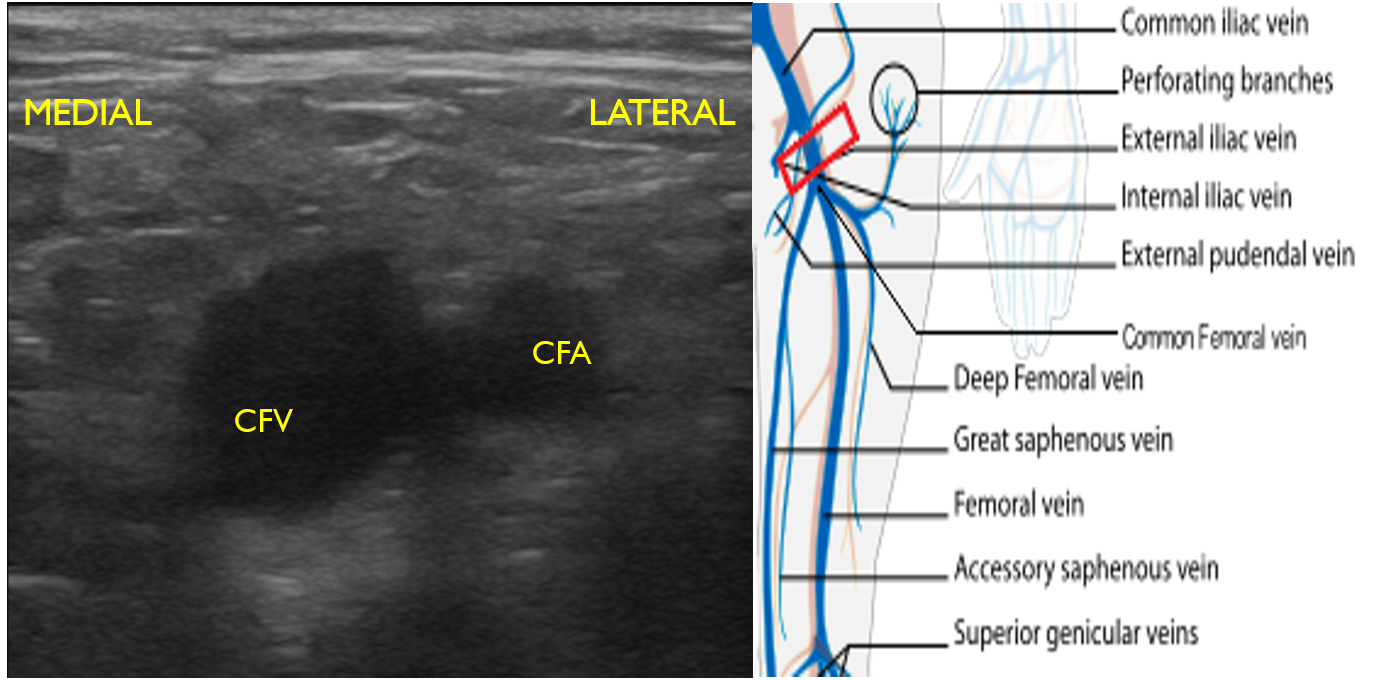

- Identify the inguinal crease at the very proximal medial thigh and place the transducer in a transverse orientation as indicated in Fig. 8. You should see the CFA and CFV as in the corresponding ultrasound image. If you see three vessels (CFA, CFV, SV), you are not proximal enough. Compress the CFV (Fig. 8 and 9).

- Figure 8. Common femoral vein and artery at the inguinal crease with transducer orientation indicated (red rectangle)

- Figure 9. Compression of the common femoral vein at the level of inguinal crease.